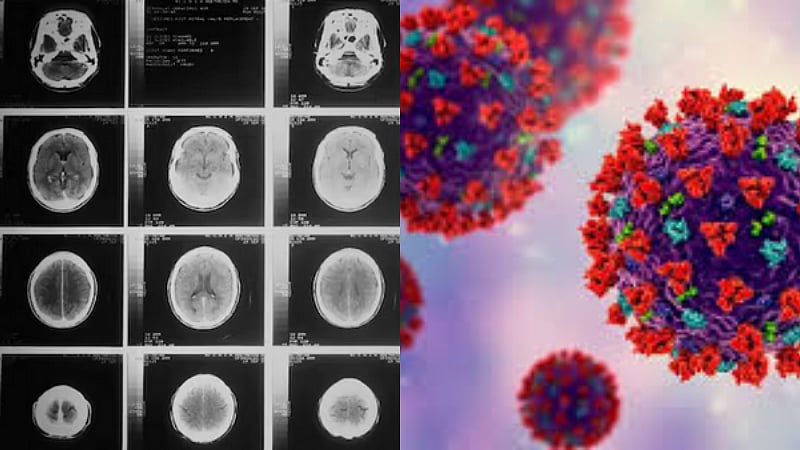

கொரோனா பெருந்தொற்றால் முதிர்ச்சி அடையும் மனிதர்களின் மூளை.. ஆய்வில் அதிர்ச்சி..!

கொரோனா பெருந்தொற்றால், மனிதர்களின் மூளை வழக்கத்தை விட ஆறு மாதங்கள் முதிர்ச்சி அடைந்துள்ளதாக புதிய ஆய்வில் தெரியவந்துள்ளது. இங்கிலாந்திலுள்ள